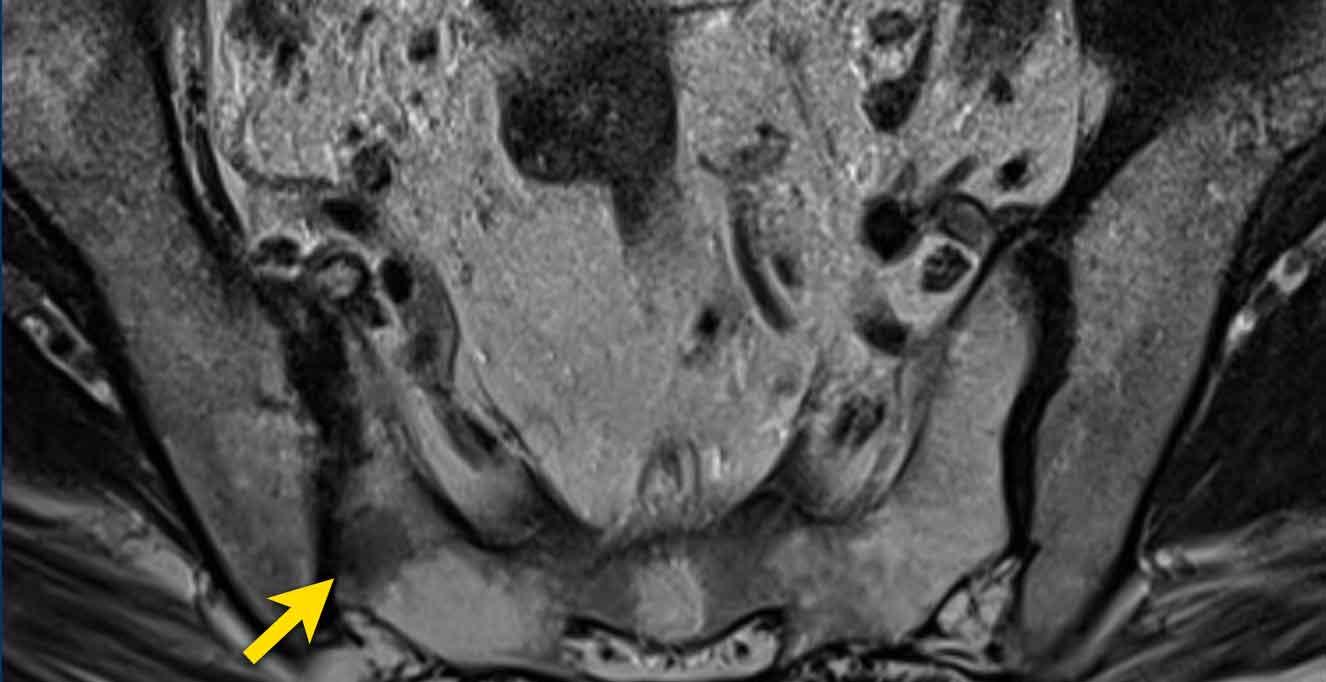

Hãy quan sát hình ảnh trước rồi tiếp tục đọc.

Các phát hiện bao gồm:

- Một tổn thương phân loại đánh giá PI-RADS 4 nằm ở vùng ngoại vi bên trái của phần giữa tuyến tiền liệt.

Giảm tín hiệu rõ rệt khu trú trên ADC (mũi tên vàng) (điểm 4), tương ứng với vùng giảm tín hiệu trên chuỗi xung T2W (điểm 4).

Điểm Gleason của tổn thương này là 3+4.

- Một tổn thương phân loại đánh giá PI-RADS 3 nằm ở vùng ngoại vi bên phải, với giảm tín hiệu khu trú nhẹ trên ADC (mũi tên xanh lá) và đồng tín hiệu trên DWI (điểm 3).

Không thực hiện DCE và không thể phân biệt thêm được.

Sinh thiết không cho thấy bất kỳ dấu hiệu ác tính nào.

Có một tổn thương ở phần trước bên phải của vùng chuyển tiếp.

Tổn thương có bờ không đều trên chuỗi xung T2W (điểm 4) và giảm tín hiệu khu trú rõ rệt trên ADC (680 mm/s) (điểm 4), kích thước không vượt quá 15 mm.

Tổn thương này tương ứng với PI-RADS mức 4.

Sinh thiết dưới hướng dẫn kết hợp MRI-Siêu âm cho kết quả Gleason 3+4.

Tại vùng ngoại vi bên phải có một vùng giảm tín hiệu nhẹ hình nêm (điểm 2) không có đặc điểm nghi ngờ trên DWI/ADC (điểm 2).

Tổn thương được xếp loại PI-RADS mức 2. Vùng này lành tính và nhiều khả năng tương ứng với teo tuyến hoặc tổn thương viêm khu trú trên mô bệnh học.